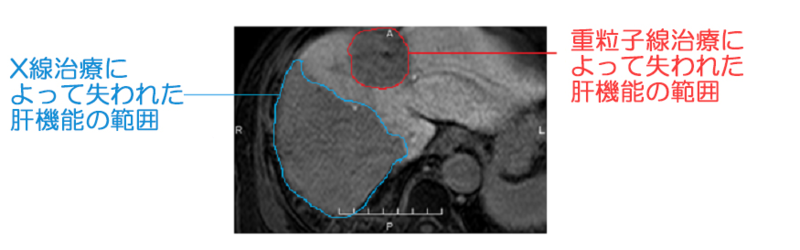

この画像は2回肝細胞がんを患い、重粒子線とX線の2種類の放射線治療をされた患者さんの肝臓を、MRIで撮影した画像です。赤の線が重粒子線治療の被ばくによって失われた肝機能の範囲、青の線がX線治療の被ばくによって失われた肝機能の範囲を表しています。

体内を突き抜ける性質であるX線の場合、がん組織に高い線量を照射するために多方向から分散して照射する必要があります。そのため、X線が通り抜けた広い部分が放射線の影響を受け障害を生じます。一方で、この画像から分かるように、X線治療よりも重粒子線治療による被ばく範囲のほうが狭くなっています。ブラッグピークを持つ粒子線治療であれば、ブラッグピークを過ぎると細胞に与える影響力は大幅に減少するため、粒子線治療は正常組織の障害が少なくてすみます。

このように、ブラッグピーク以外の部分ではX線よりも影響力が低く、正常組織への影響を抑えられることが、粒子線治療のメリットです。

2つめは、前項でお伝えしたとおり、照射する範囲が狭く被ばくする範囲が抑えられるため、より多くの肝機能が残せることです。肝細胞がんには、肝臓内の別の領域に再発しやすいという特徴があるため、後の治療のためにも肝機能をできるだけ残しておくことが重要です。

一方、X線治療は広い範囲で被ばくしやすく、肝臓の半分近くの肝機能が失われることがあります。X線治療によって肝細胞がんを治療した後に、再発して治療が必要になっても、肝機能が不十分なため追加の治療が困難となる場合があります。